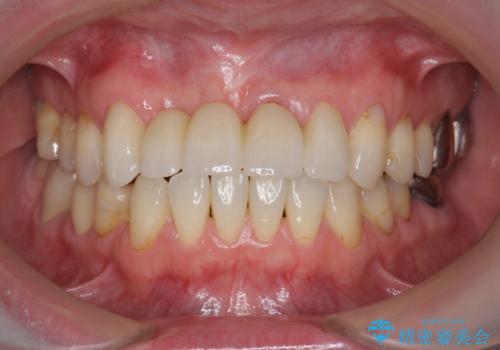

前歯が折れた 前歯部審美セラミックブリッジ治療

- ブリッジの根元が折れ、審美性の改善・治療を求めて来院されました。

保存の難しい歯を抜去しロングブリッジによる補綴を選択しました。

かみ合わせの観点からインプラント治療は難しく、入れ歯も希望されなかったためブリッジによる補綴を選択しました。

- 57万円(仮歯・ファイバーコア・ジルコニアクラウン×5)費用は治療当時の料金となります